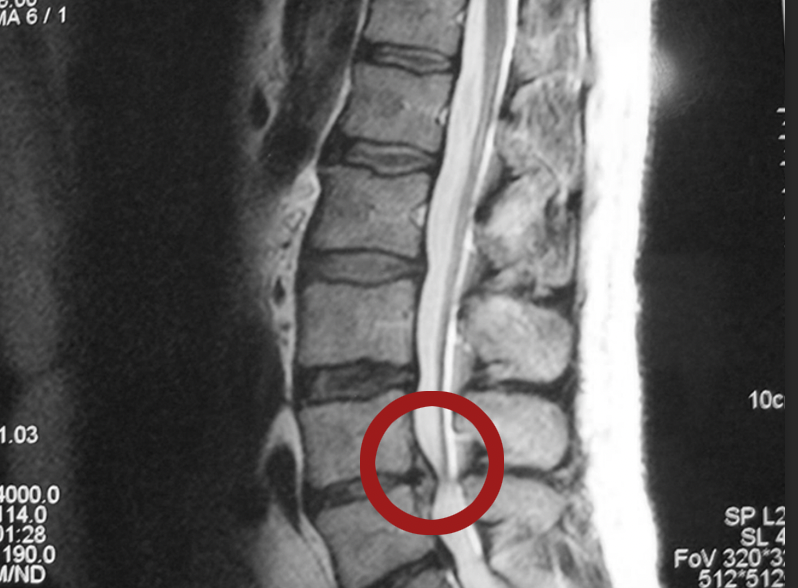

Межпозвоночная

грыжа -